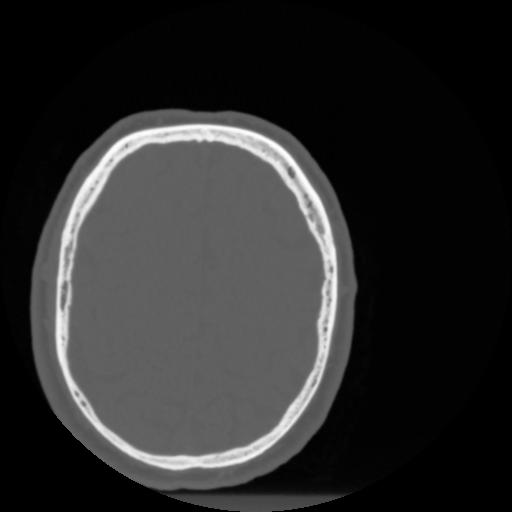

4 CEREBRO,,Vol,0.5,CEREBRO,,